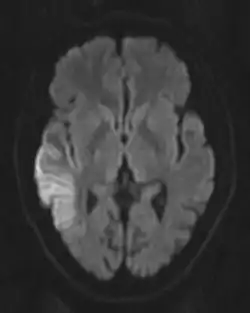

![]() Obraz MR-DWI głowy pacjenta z MELAS, widać pasmo intensywnego sygnału z kory mózgowej (ograniczenie dyfuzji), co odpowiada obrazowi klinicznemu (splątanie, ogniskowy deficyt neurologiczny) | |

- incydenty udaropodobne do 40. roku życia, początkowo przede wszystkim w płatach ciemieniowych i potylicznych, także w innych częściach mózgowia